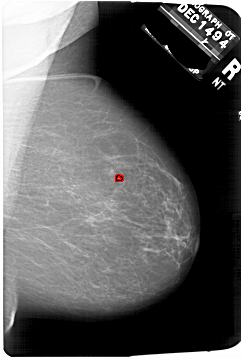

A_1751_1.RIGHT_MLO

RIGHT_MLO LINES 6871 PIXELS_PER_LINE 4576 BITS_PER_PIXEL 12 RESOLUTION 43.5 OVERLAY

FILE: A_1751_1.RIGHT_CC.OVERLAY

TOTAL_ABNORMALITIES 1

ABNORMALITY 1

LESION_TYPE CALCIFICATION TYPE PLEOMORPHIC DISTRIBUTION CLUSTERED

ASSESSMENT 4

SUBTLETY 2

PATHOLOGY BENIGN

TOTAL_OUTLINES 1

BOUNDARY